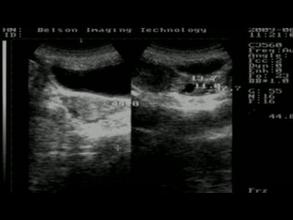

1.盆腔和阴道B超:可早期发现子宫肌瘤、卵巢囊肿等病变。